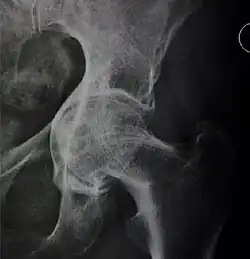

X-ray of hip dysplasia

![Normal hip.[3]](./_assets_/X-ray_of_measurements_on_a_normal_hip.jpg)

![Hip dysplasia.[3]](./_assets_/X-ray_of_measurements_in_hip_dysplasia.jpg)